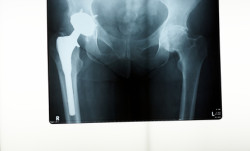

A x-ray of a hip replacementA new hip replacement lawsuit was recently filed in federal court alleging that Biomet’s metal on metal hip implant has a design defect that causes serious hip replacement problems in patients that have the device implanted.